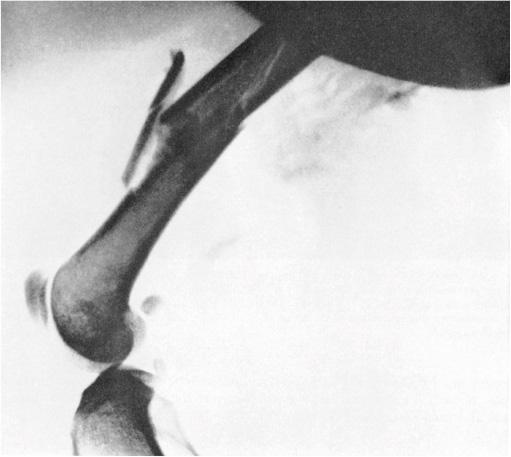

Рис. 2. Рентгеновский снимок, сделанный в лаборатории Эдмунда Ньютона Харви во время Второй мировой войны. James Boyd Coates, ed., Wound Ballistics (Washington, D.C.: Office of the Surgeon General, Department of the Army, 1962), figure 69

В 1942 году, в разгар Второй мировой войны, в лаборатории Принстонского университета группа изучения раневой баллистики экспериментировала на находящихся под наркозом кошках. Кошки имитировали солдат, точнее военнослужащих мужского пола, а пули уменьшались в размере так, чтобы соответствовать соотношению между телом среднего мужчины и стандартной армейской пулей (рис. 2). Исследователи хотели выяснить, как именно должна выглядеть и выстреливаться пуля, чтобы причинить максимальный ущерб. Это и есть раневая баллистика: поиск путей модифицирования баллистических свойств пули, чтобы сделать ее максимально смертоносной. В ходе работы эта группа вывела уравнение замедления, описывающее воздействие пули на живые ткани кошки1.